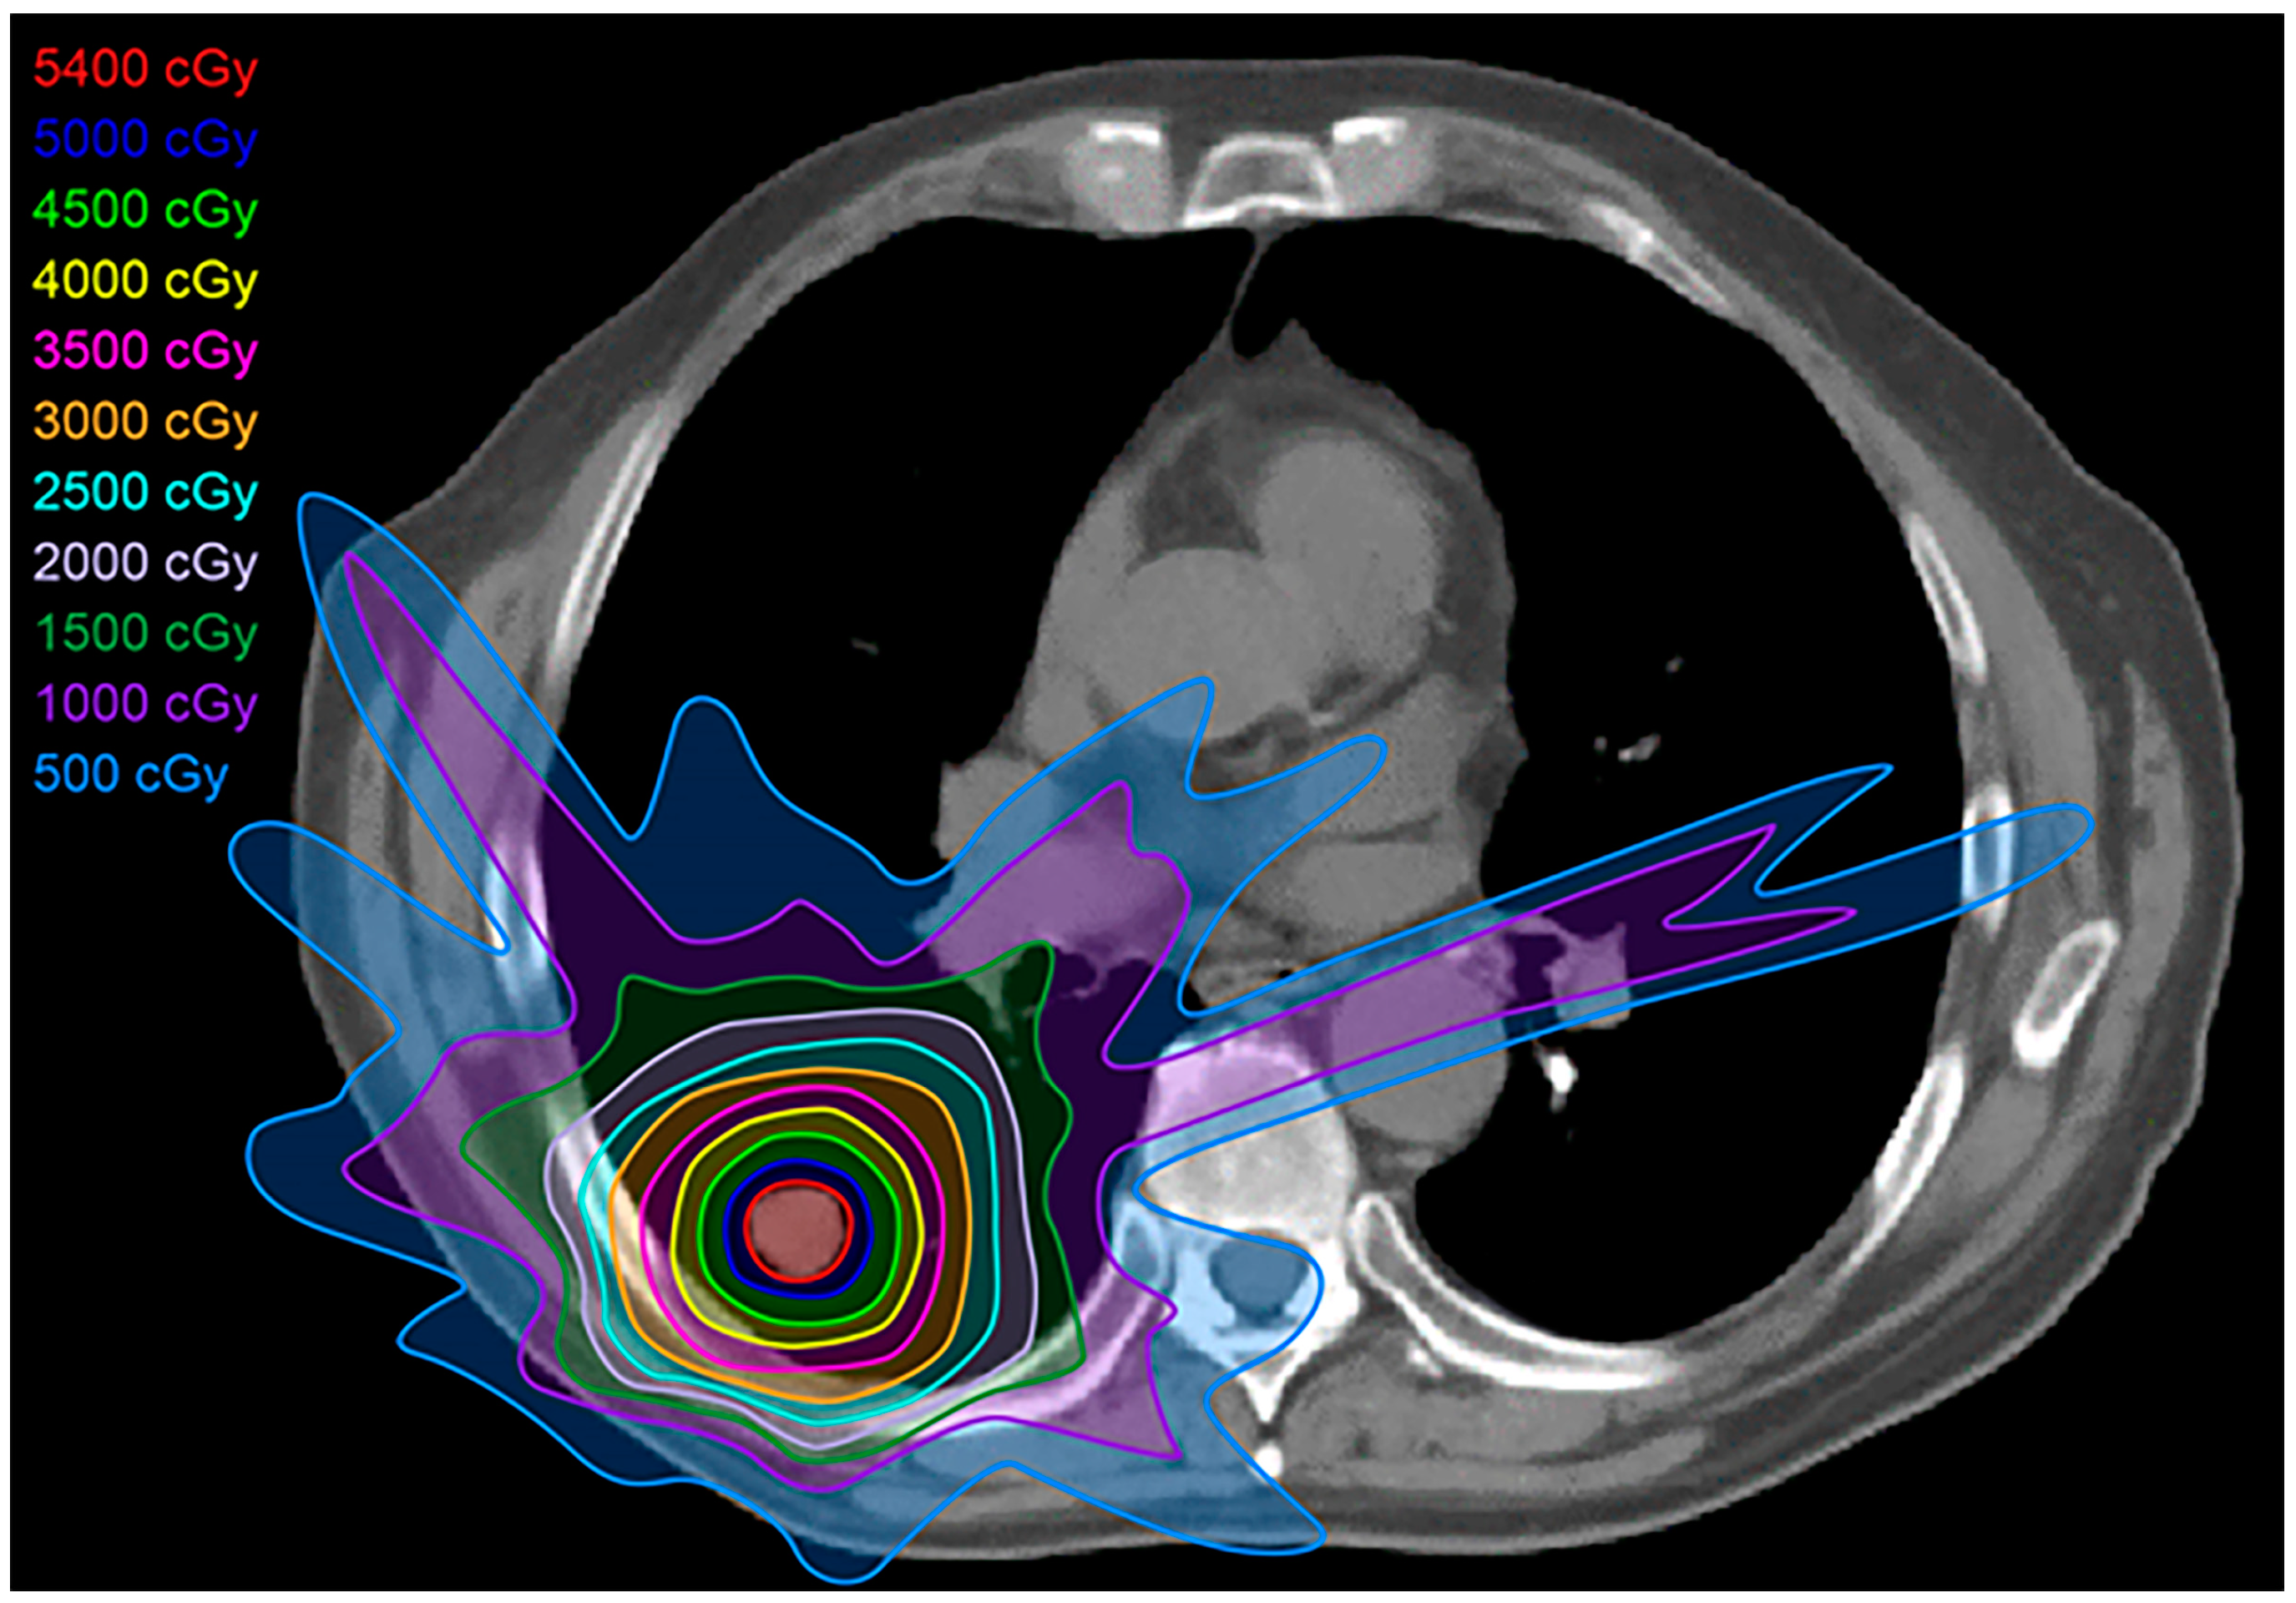

2.6. Proton Therapy